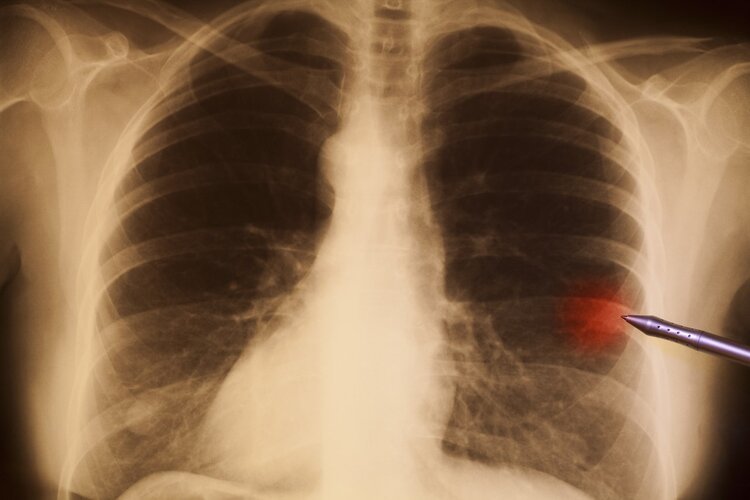

肺癌的胸片

肺癌的胸片,

(图 混合型肺癌

大家看一下这张胸片(左肺门的圆形阴影是什么?